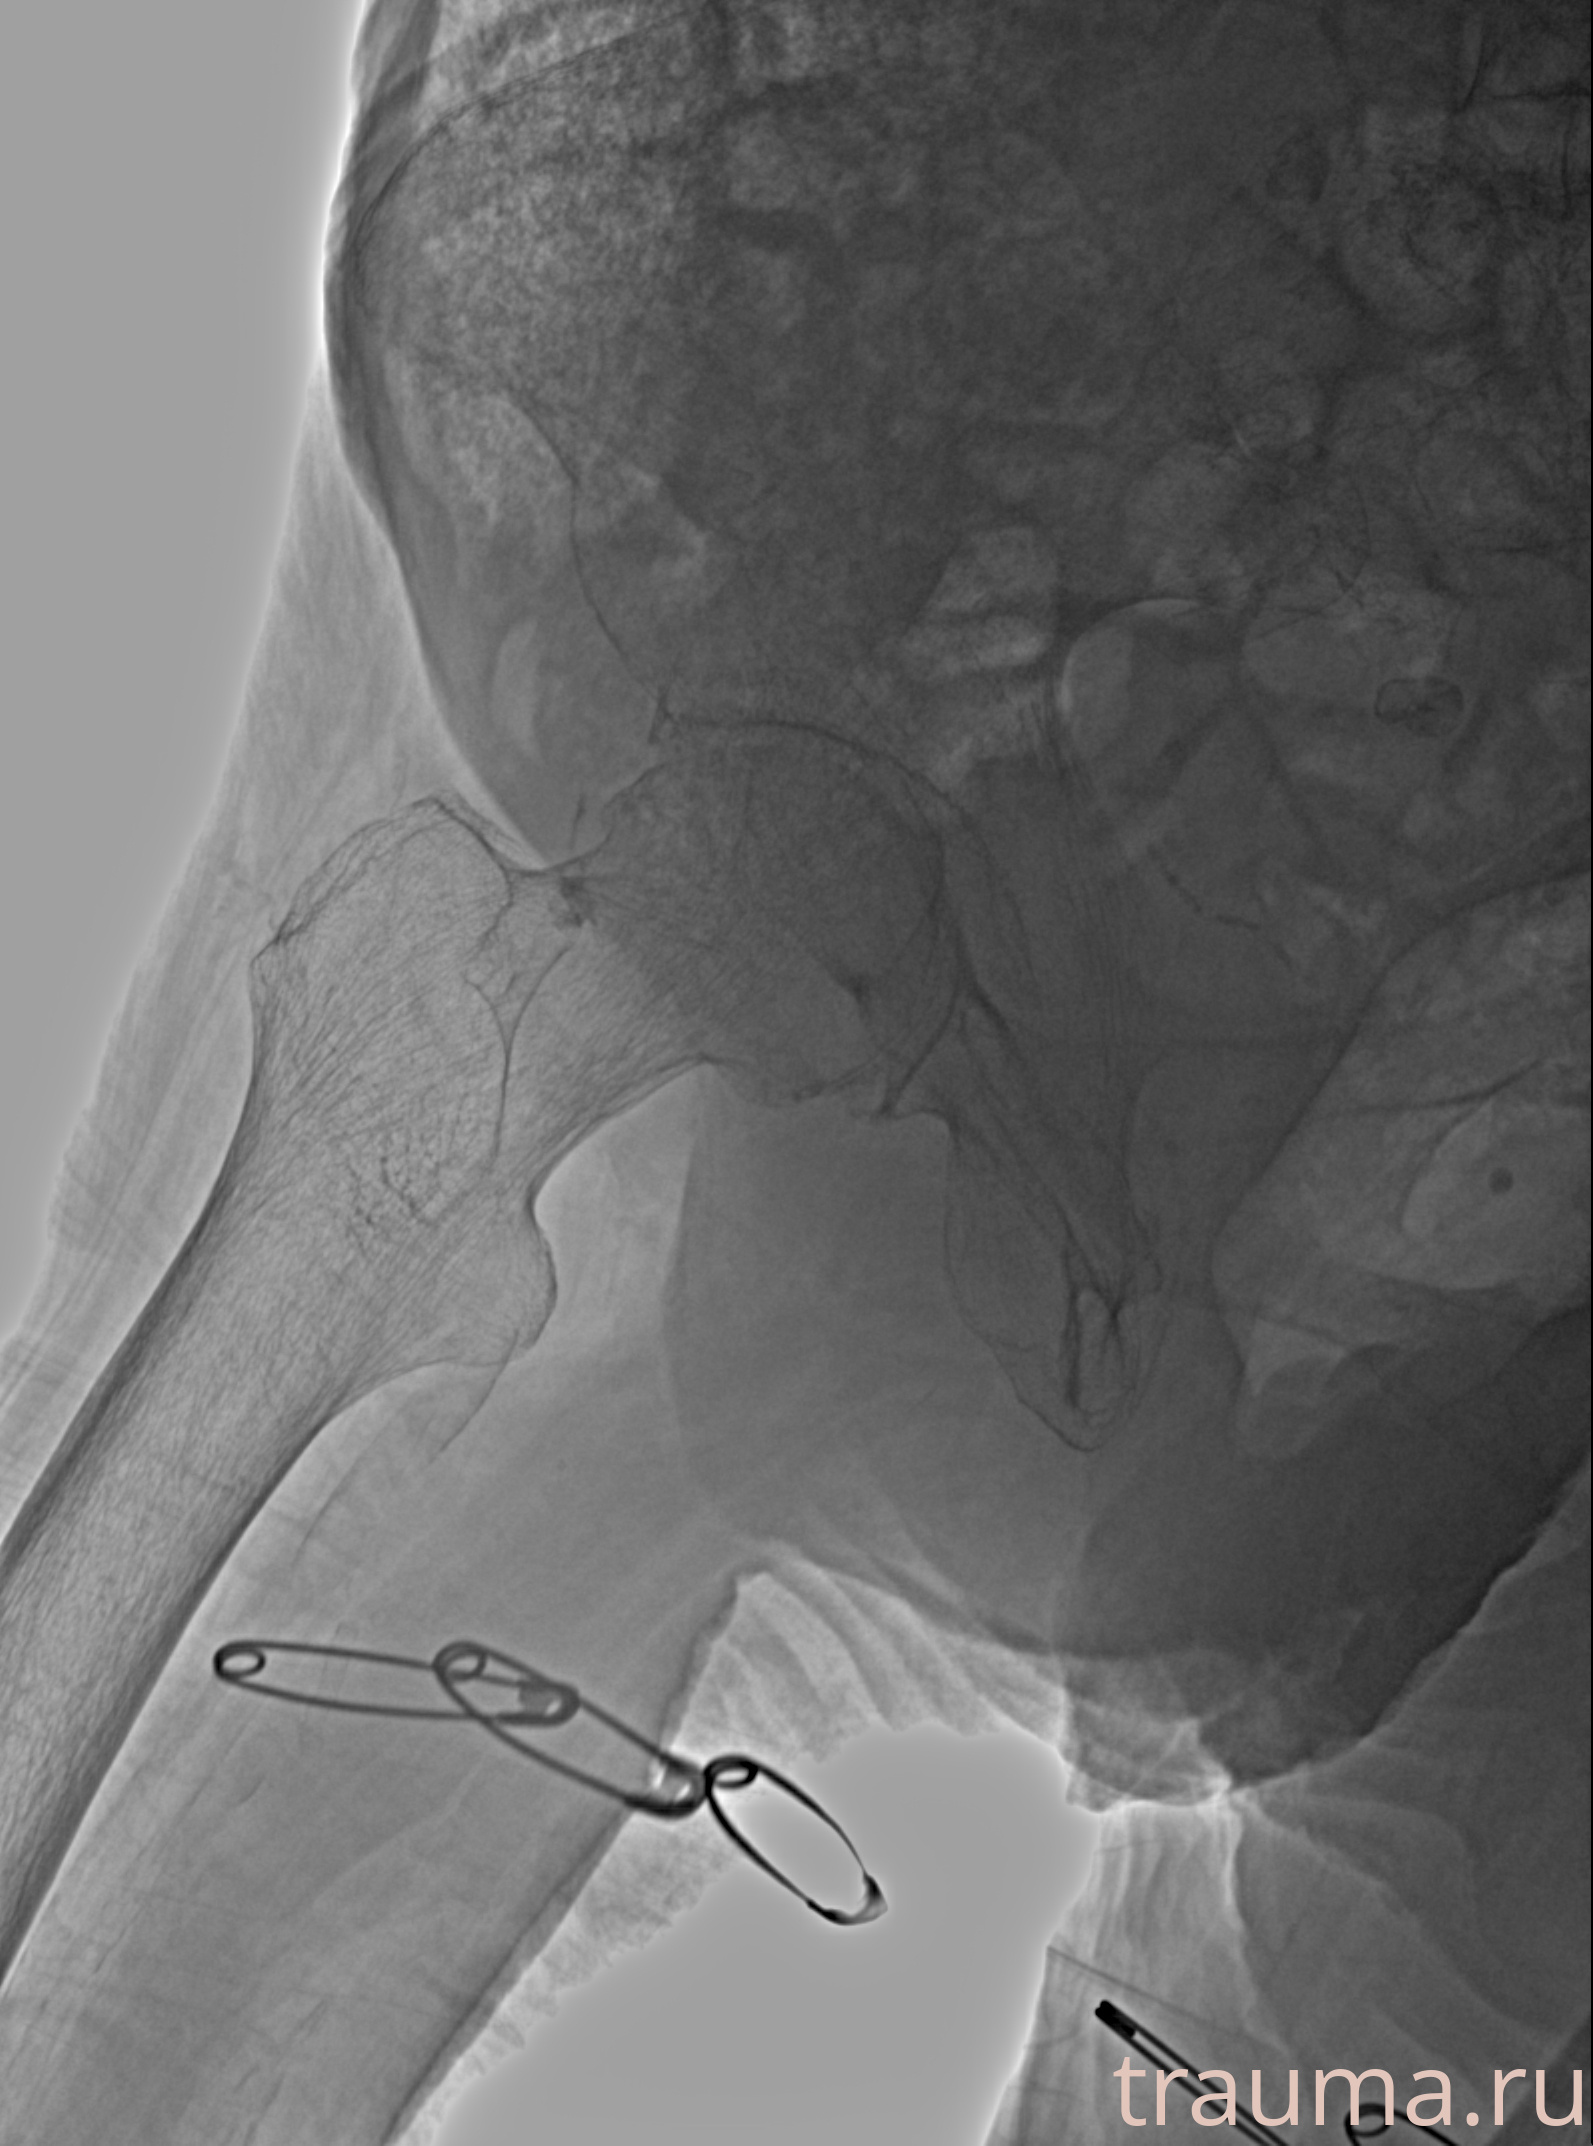

Рентгенограммы

Рентген на дому: по вашему адресу приезжает врач-рентгенолог, травматолог-ортопед с мобильным рентгеновским аппаратом, проводит диагностику травмы или заболевания, делает необходимые рентгенограммы, дает рекомендации по дальнейшему лечению. Получить качественные снимки в домашних условиях возможно благодаря уникальной методике, разработанной МосРентген Центром для института  Склифосовского